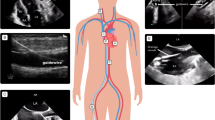

Under V-V ECMO, highly protective mechanical ventilation is obtained by reducing the ventilatory load (pressures, volumes and rate) on the native lung, whose gas exchange function is undertaken by an artificial (membrane) lung. The membrane is perfused by high blood flows (normally 4–6 L/min), and the “sweep gas” (with a variable concentration of oxygen) is forced through the membrane’s fibers, with efficient oxygen and carbon dioxide exchange [3]. The resulting oxygenated and de-carboxylated blood is then mixed in the right atrium with the venous return not passing the membrane lung, and finally flows through the patient’s native lung, which contributes (at a variable degree) to the final PaO2 and SaO2. However, the two most important determinants of oxygenation under V-V ECMO are the extracorporeal blood flow (Fig. 1) and the fraction of oxygen in the sweep gas (FmO2).

Extracorporeal oxygen delivery (\(\dot{V}\) O2ML)/total oxygen consumption (\(\dot{V}\) O2TOT) and extracorporeal carbon dioxide removal (\(\dot{V}\) CO2ML)/total carbon dioxide production (\(\dot{V}\) CO2TOT) as a function of extracorporeal blood flow (BF) at steady state in an adult patient. \(\dot{V}\) O2TOT = 250 mL/min and \(\dot{V}\) CO2TOT 200 mL/min. Veno-venous extracorporeal oxygenation support (V-V ECMO), veno-venous extracorporeal CO2 removal (V-V ECCO2R)

Differently from ECMO, ECCO2R uses lower blood flows, smaller circuits, membranes, and cannulas. As such, the main effect of this technique is to lower carbon dioxide, without any relevant effect on oxygenation (see Fig. 1). Indeed, the principal determinant of carbon dioxide removal is the amount of sweep gas flow. Accordingly, ECCO2R uses blood flows in the range of 300–1500 mL/min and sweep gas flows up to 8–10 L/min. Clinical indications for ECCO2R are still debated, but it is presently applied in severe exacerbations of chronic obstructive pulmonary disease (COPD) (with the aim of reducing the rate of intubation and duration of mechanical ventilation) and in moderate ARDS (to reduce the ventilatory load to allow “ultra-protective” ventilatory settings) [4, 5]. Combinations of ECCO2R with continuous renal replacement therapy (CRRT) have been recently described in patients with ARDS and acute kidney injury [6, 7].

Current oxygenators are based on the juxtaposition of multiple hollow fibers creating channels, with the most commonly used material being polymethylpentene (PMP). Compared to older materials, these fibers have better durability, cause less hemolysis, and cause less plasma leakage. In the oxygenator, O2 transfer is dependent on: (a) surface area and diffusion characteristics of the membrane; (b) O2 partial pressure (PO2) gradient between blood and sweep gas; and (c) blood flow. The surface area has been substantially increased by using hollow fibers and should not be a limiting factor in current adult oxygenators [28]. Increasing blood flow increases the number of fibers used and maximizes contact. However, increased blood flow can decrease transit time and reduce oxygenation. When 100% oxygen is used as sweep gas, the blood downstream the membrane lung has a PO2 up to 300–500 mmHg, with a maximized O2 content [29]. Further, the extracorporeal oxygen delivery at a given blood flow is highly dependent on the oxygen content of the blood entering the membrane lung. Almost 5 L/min of blood flow are required to provide an oxygen transfer comparable to the total body oxygen consumption of an adult patient (Fig. 1), assuming a hemoglobin saturation of 70% of the blood entering the membrane lung. Meanwhile, carbon dioxide is quickly transferred from the blood to the sweep gas according to the partial pressure gradient across the membrane. High sweep gas flows allow clearing an amount of CO2 comparable to 60% of the total CO2 production, while blood flows above 2–3 L/min may be required to remove an amount of CO2 comparable to the total CO2 production of an adult.